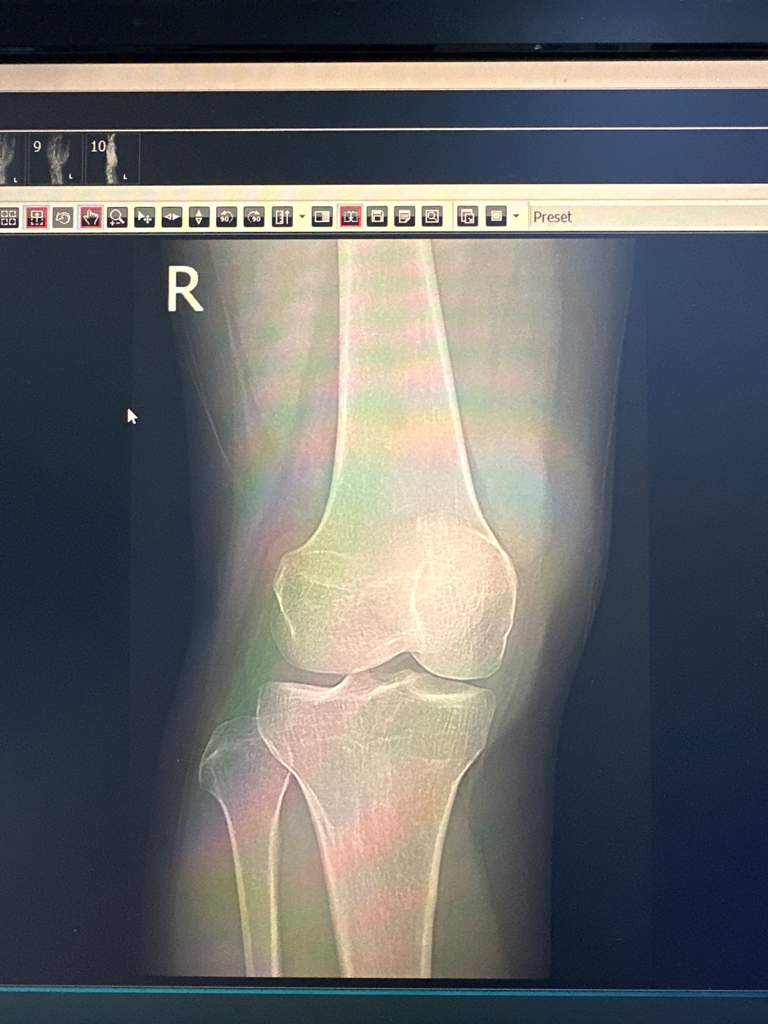

전공이 아니라 말씀드리기가 조심스럽지만 왼쪽 무릎 위쪽의 대퇴골에 덩이로 추정되는 것이 보이고 있어 추가검사를 요하는 것 같습니다. 골종양을 확인해야만 하는 상황이라 보입니다만 강력히 권한 정도가 아니라면 악성을 의심하시는 것 같지는 않습니다.